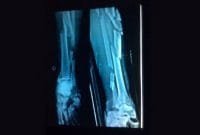

Foto Ronsen Kaki M Fadli yang beredar belum tentu Benar

M Fadli, pembalap AHRT yang mengalami kecelakaan kemarin, Minggu (7/6/2015) menjalani operasinya dengan lancar. Sebelum dioperasi, Tim medis Sirkuit Sentul […]